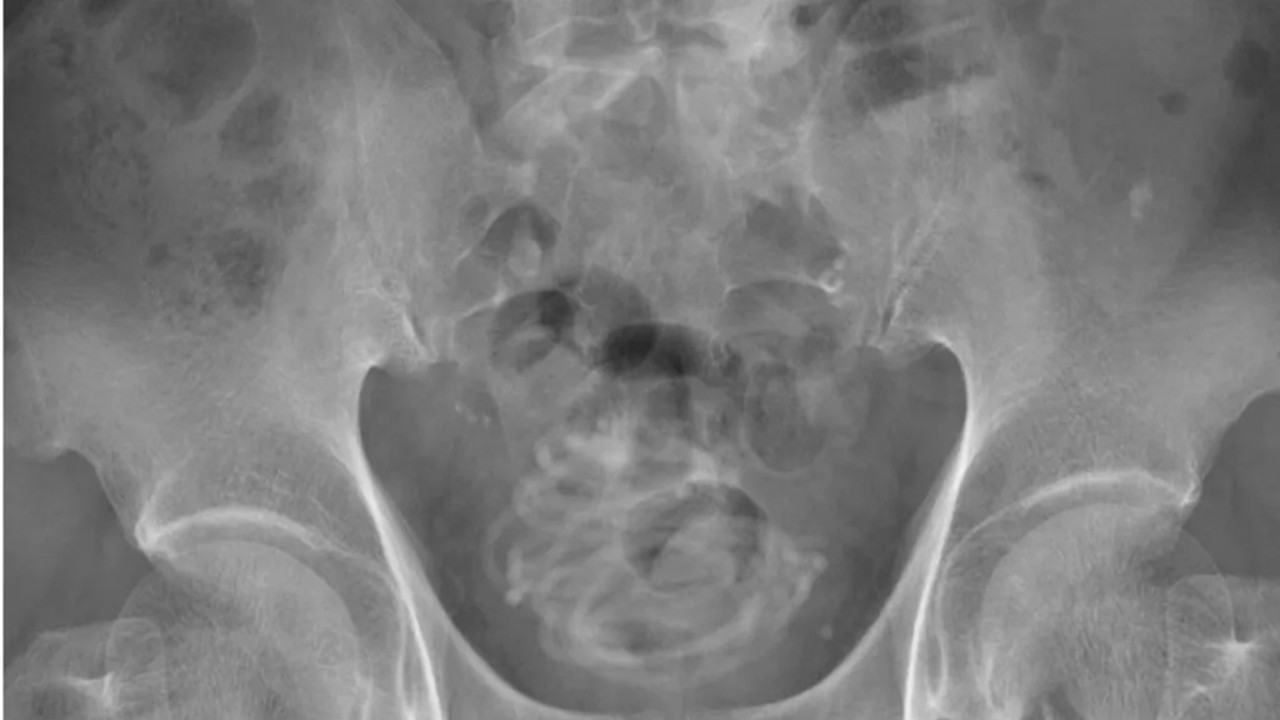

Olay Japonya’da meydana geldi. Ağrılar içinde hastaneye kaldırılan ismi açıklanmayan adam kasıklarında acı hissettiğini söyledi. Dokkyo Tıp Fakültesi’nde gerçekleşen olayda adamın tuvalete çıkarken yanma hissi hissettiği de belirtildi. Röntgen çekildikten sonra adamın penisinden içeri atlama ipi yerleştirildiğini gören doktorlar şaşkına döndü. İngiliz medyasında yer alan haberlerde hastane çalışanları, “Kariyerimiz boyunca bu kadar aşırı bir şey görmedik” açıklamasını yaptı.

Yapılan zorlu bir ameliyat süreci sonrasında adamın penisinden atlama ipinin çıkarıldığı belirtildi. Atlama ipinin tutma kısımlarının olmadığı ve 2 metreden uzun olduğu belirtildi. İpin, idrar torbasında düğüm olduğu ve bu sebeple ameliyatın riskli geçtiği de belirtildi.

İpin ince olduğuna dikkat çeken doktorlar, ipin düğüm olması sebebiyle idrar torbasına bir delik açarak cerrahi bir müdahale gerçekleştirildiğini de duyurdu. Ameliyatın başarılı geçmesi için idrar torbasının 3-D modelinin yapıldığı ve bu sayede doktorların nasıl müdahale edeceklerinin anlaşıldığı açıklandı.

Tokyo’nun 160 kilometre uzağında yaşanan olay Urology Case Reports isimli tıp dergisinde yayınlandı. Araştırmayı kaleme alan ve operasyonda da yer alan Profesör Toshiki Kijima, “Tarama ve modelleme teknolojisi ameliyatın başarılı geçmesine katkı sağladı” dedi. Fakat bilim insanları 79 yaşındaki adamın, bu ipi neden cinsel organına soktuğunu açıklamadığını dile getirdi.